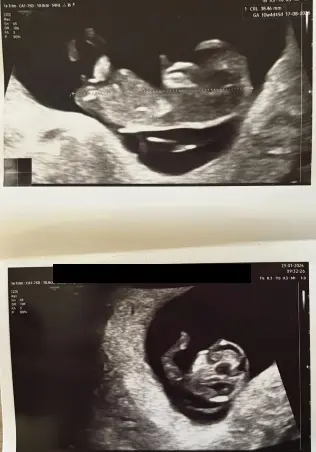

We hebben gisteren een uitgebreide echo gehad in het ziekenhuis, het bleek dat het vocht relatief ‘gunstig’ zat. Wel was de verdikte nekplooi iets gegroeid naar 3,9 mm, maar volgens de specialist viel dat binnen de marge en ook omdat de baby iets groeit. Voor wat ze kon zien op de echo bij een termijn van 11 weken leek het er goed uit te zien, ze zag alleen iets van een uitstulpsel bij de navel, maar dat kon ze nu nog niet goed genoeg zien. Wat voor ons een enorme opluchting was, is dat de kans nog steeds 70% is op een gezond kindje!

Vandaag hebben we direct de vlokkentest gedaan en binnen 3 dagen ontvangen we de snelle uitslag. Komt daar niks uit dan blijft het natuurlijk spannend, maar we zijn alweer iets positiever!

1 uur geleden

Hee! Wij hebben dit ook gehad (vastgesteld bij termijnecho, eigenlijk iets te vroeg). Bij de termijnecho werd 3.8 mm gemeten en vocht om het kindje heen. Doorverwezen naar het ziekenhuis voor een GUO 5 dagen later, vocht was niet te zien maar nekplooi alsnog wel 4.1 mm. Op basis daarvan hebben wij ervoor gekozen om een vlokkentest te laten afnemen, dit is gebeurd in het isala ziekenhuis. Uiteindelijk alle uitslagen "goed" teruggekomen (eerst sneltest 3 syndromen) en daarna uitgebreid dna onderzoek.